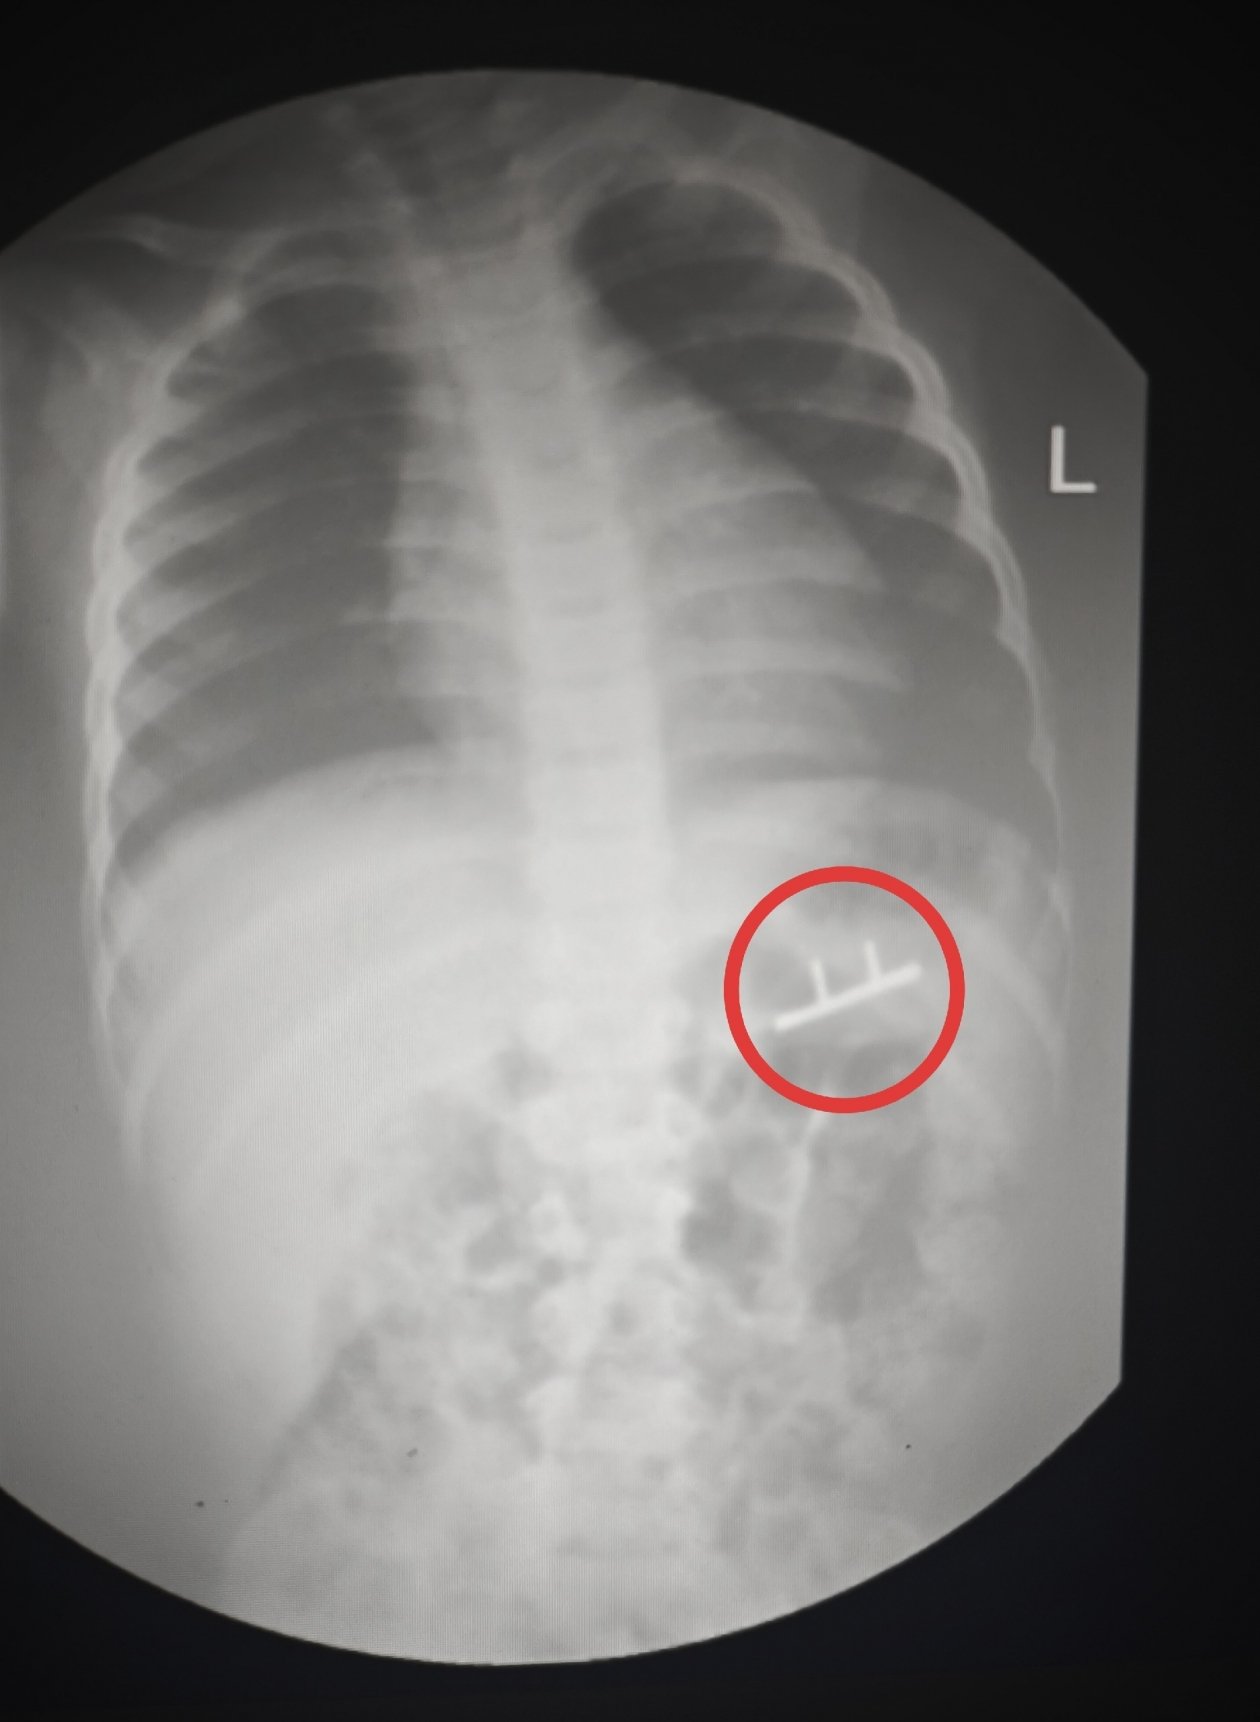

Stavropol.Media, 3 февраля. Проволока, бутылка и батарейки — эти и многие другие предметы извлекли из ставропольцев в 2025 году. Подборкой необычных находок внутри пациентов поделилась городская клиническая больница Пятигорска в своих соцсетях.

Специалисты удаляли монеты, металлические пластины с шурупами, а ещё фруктовые косточки и коронки.

"Случаи курьёзные, но проблема на самом деле серьёзная — ежегодно в ГКБ Пятигорска поступают десятки пациентов с инородными телами. Среди них немало детей. И им, как правило, требуется экстренная медицинская помощь", — напомнили в больнице.